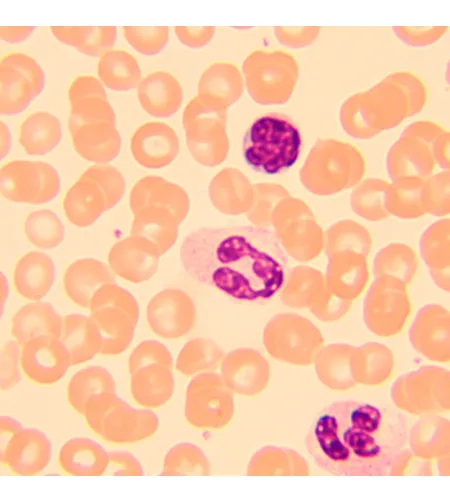

MAGUS Bio 250B biologinis mikroskopas yra optinis instrumentas, skirtas ploniems skaidriems ir peršviečiamiems objektams tirti. Ryškaus lauko mikroskopija perduodamoje šviesoje yra pagrindinis mikroskopijos metodas. Mikroskopas gali būti aprūpintas papildomais priedais tamsaus lauko, fazinio kontrasto ir poliarizacijos technikoms naudoti. Aukštos kokybės optika su papildomomis galimybėmis išplėsti savo galimybes, paprasta naudoti mechanika ir protingas dizainas daro šį mikroskopą puikiu pasirinkimu laboratoriniams darbams, tyrimams ir mokymui.

| Tyrimo metodas | Bright Field |